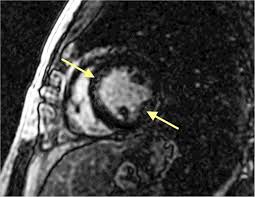

Cardiac Mri Shows Lower Degrees Of Myocarditis In Athletes Recovered From Covid 19 Imaging Technology News

Cardiac Mri Shows Lower Degrees Of Myocarditis In Athletes Recovered From Covid 19 Imaging Technology News from www.itnonline.com

Sie kann akut oder chronisch verlaufen. Was heute alles möglich ist. Mrt in der diagnose und monitoring neurodegenerativer erkrankungen. Classified as idiopathic, these cases are attributed to genetic factors, viral myocarditis, and autoimmune mechanisms. Wir führen diese untersuchung in kooperation mit der radiologie. Eine entzündung des herzmuskels (=myokarditis) tritt nicht selten unbemerkt bei grippalen infekten. Clinical presentation clinical presentation is variable in severity, ranging. Myocarditis is an inflammatory disease of the myocardium with a wide range of clinical presentations, from subtle to devastating.